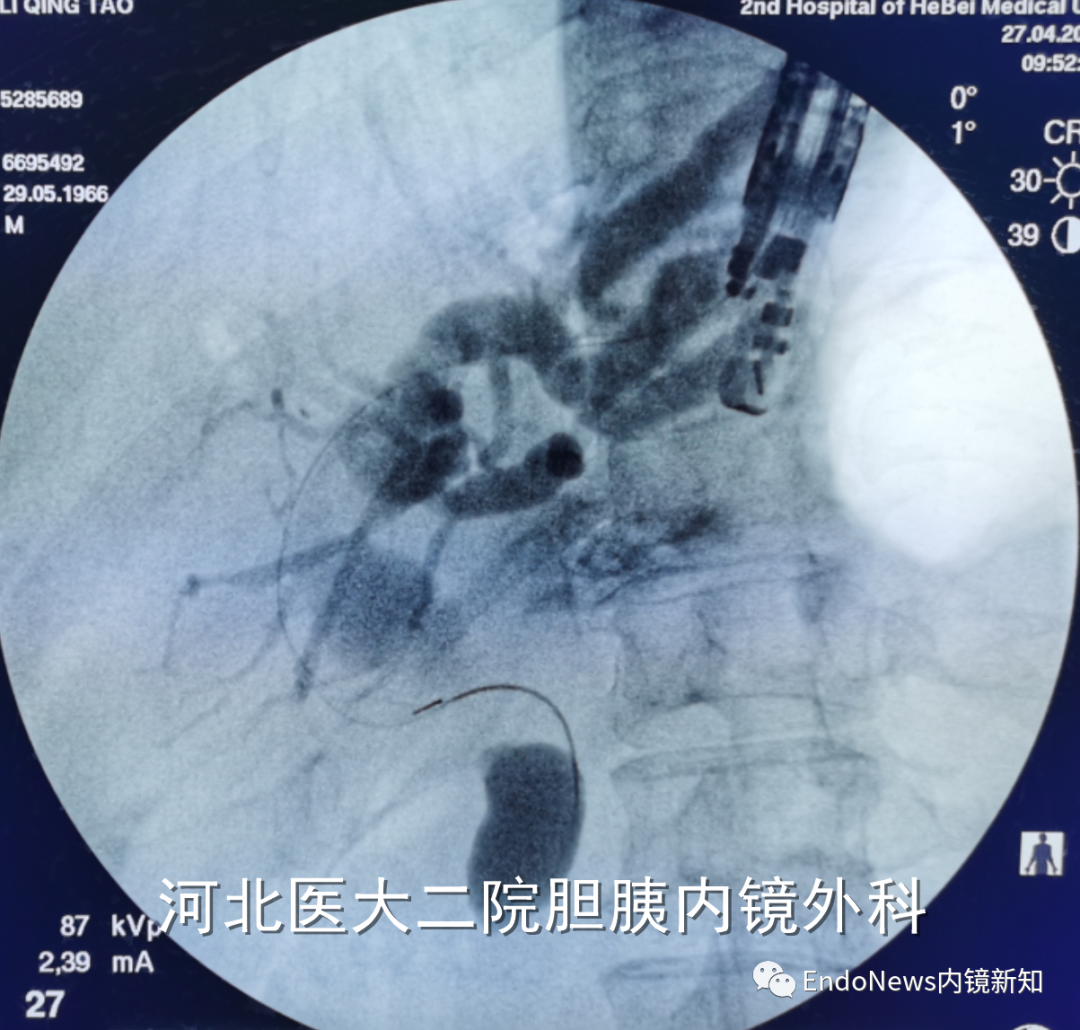

行经十二指肠胆管穿刺(CDS)时一般不需要考虑以上问题,但如因某些特殊原因涉及到会师操作时可能涉及到导丝自胆总管上游朝向下游的超选。一般情况下,CDS的时候穿刺针的方向是朝向肝内的,比如下图:

如果这个时候放支架行CDS就可以结束手术了,如果需要做顺行或者会师,就需要使导丝返折180°朝向胆管下游方向穿出十二指肠乳头。